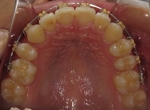

CASE1

前歯の歯並びが悪いのが一番気になります。

右側では良く噛めません↓(16歳/女性)

概要・担当医コメント:叢生・右側咀嚼障害↑

マルチブラケット装置/動的治療期間26ヶ月(23回)

/費用概算:60万円

高校の部活も矯正も両方頑張れたそうです。

上顎右側の小臼歯を1本のみ抜歯させていただき,あとは上下の歯列アーチ形態の修正にて矯正できました。